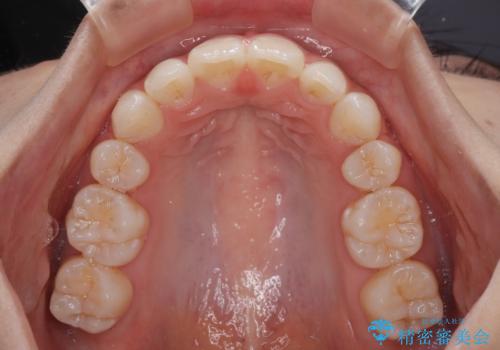

- 口を閉じたときに飛び出してしまう上顎前歯を気にして来院された患者様です。

下顎はデコボコが気になっていたため、上下左右第一小臼歯4本を抜去して、ワイヤー装置にて口元の突出感を改善するよう矯正治療を行うこととしました。

下唇に前歯が当たって跡が残ってしまう状態でしたが、スッキリとした口元に仕上げることができました。